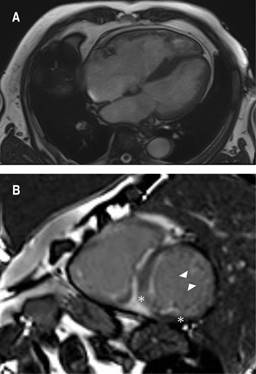

A transthoracic echocardiogram revealed a dilated left ventricle with end-diastolic diameter 60 mm, mild to moderate septal hypertrophy and severely depressed systolic function (20% LVEF by Simpson) due to global hypokinesia. He also had biatrial dilatation, a severely dilated right ventricle with depressed systolic function, mild regurgitation of the four heart valves, mild pulmonary hypertension and dilated inferior cava vein. A cardiovascular magnetic resonance (CMR) showed biventricular dilatation and systolic dysfunction (Figure 1A). High native T1 values (1304 milliseconds) and an increase in extracellular volume (40 with a 43.2% hematocryte) were reported and T1 PSIR sequences disclosed epicardic mid inferolateral, inferoseptal, subendocardial anterior and anterolateral late gadolinium enhancement (Figure 1B). These findings were compatible with infiltrative cardiomyopathy and suggestive of cardiac amyloidosis. At this point, a 99mTc-DPD bone scintigraphy, a blood and urine analysis to evaluate a possible monoclonal component -according to the latest recommendations on the diagnosis of cardiac amyloidosis4 and cardiac catheterization were requested. ATTR cardiomyopathy compatible images were reported in the scintigraphy with a significant Perugini grade 3 heart uptake of the radiotracer (Figure 2). The coronary angiography showed only mild irregularities in the left anterior descending and circumflex coronary arteries without significant obstructive lesions. The search for light chain immunoglobulin monoclonal gammopathy was negative, AL amyloid heart disease was ruled out, so ATTR cardiomyopathy was diagnosed.

Figure 1: Cardio magnetic resonance. A) Four chamber view in a cine sequence frame with biventricular dilatation (telediastolic left ventricle normalized volume 151mL/m2, right ventricle 110 mL/m2) and septal moderate to severe hypertrophy. B) Short axis view in a late gadolinium enhancement T1 PSIR sequence. Epicardic mid inferolateral and inferoseptal (*) and subendocardial anterior and anterolateral (tips of the arrows) late gadolinium enhancement.